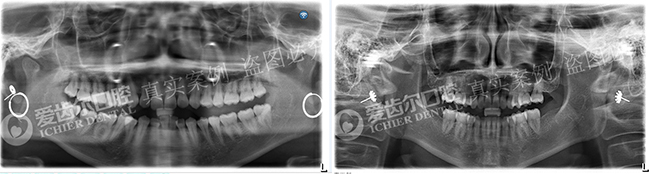

矫正前后全景片